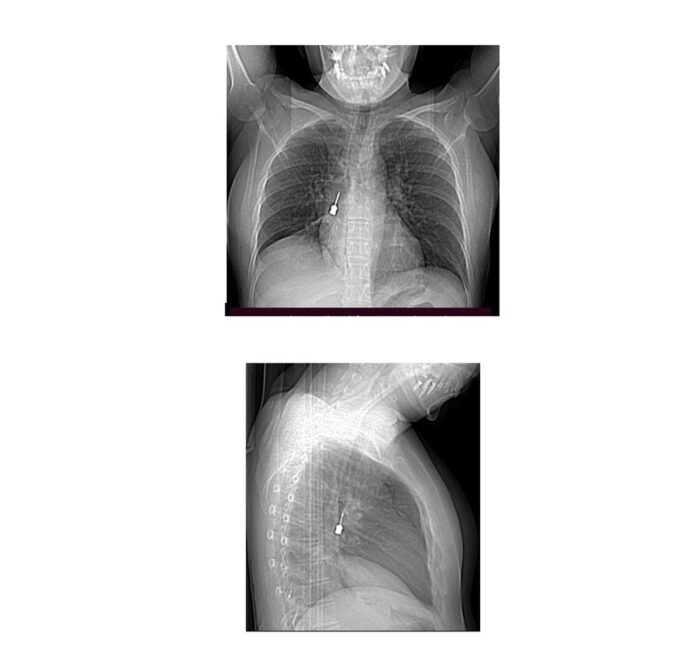

La paziente è giunta al Pronto Soccorso del G.O.M. esibendo un esame di diagnostica per immagini (Tomografia Computerizzata) eseguito a causa di una tosse persistente e di un forte dolore a livello toracico. La TC mostrava la presenza di un corpo estraneo metallico pericolosamente incastrato nel bronco lobare inferiore del polmone destro e un concomitante pneumomediastino, ossia la presenza di aria nello spazio compreso fra i due polmoni.